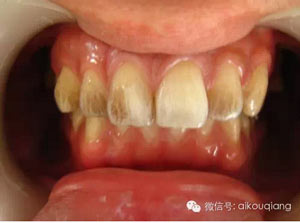

定期洗牙是目前最有效的治療牙周疾病的方式。下面是洗牙前后的對(duì)比圖:

男性成年人喜歡喝茶、抽煙,造成牙齒表面色素沉著,很不美觀

洗牙(潔治)后,潔白如一